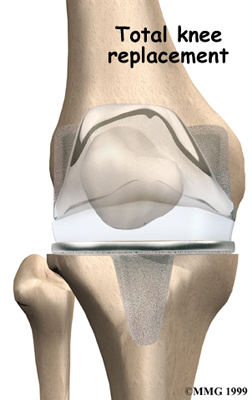

Artificial Knee Replacement

An artificial knee replacement is the ultimate solution for advanced knee OA.

Surgeons prefer not to put a new knee joint in patients younger than 60. This is because younger patients are generally more active and might put too much stress on the joint, causing it to loosen or even crack. A revision surgery to replace a damaged prosthesis is harder to do, has more possible complications, and is usually less successful than a first-time joint replacement surgery.

Related Document: FYZICAL Sun Valley's Guide to Artificial Joint Replacement of the Knee